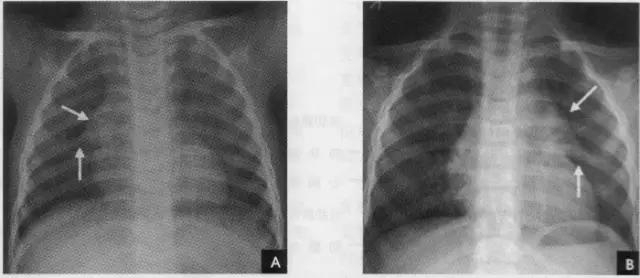

1、肋骨共12对,每根肋骨分为前肋、腋段和后肋三段:同一肋骨前后段的位置不同,一般第6前肋与第10后肋等高。前段扁薄,密度略低,自外上向内下倾斜走行并形成肋弓;后段圆厚,密度略高。呈水平状向外下走行;在无变异的情况下,两侧肋骨的位置及肋间隙的宽度基本对称,故肋骨及肋间隙常被用作胸部病变的定位标志。第1~10肋骨前端有肋软骨与胸骨连接,因肋软骨未钙化时不显影,故肋骨前端多呈游离状。25岁以后第1对肋软骨首先钙化,其他肋软骨随年龄增长,自下而上逐条钙化。第一肋骨常常显示不规则钙化区,尤其是中年以后。下部诸类也显示局限性的钙化,即使在成年人也是这样。在女性的软骨钙化常常示不规则的,造成斑点状形态。而在男性钙化可以局限于软骨之上下缘,造成线样阴影。有时下肋部肋软骨的钙化极为广泛,造成下肺野内带不规则的斑点状致密影。肋骨有很多种先天变异(下图),常见的有以下几种:

(2)叉状肋为最常见的肋骨变异。多发生在第3、4肋骨,表现为肋骨前端呈叉状,亦可同时伴有增宽或缩短变形;或一支膨大另一支短小;或在肋骨上仅见一骨性突起;或在分叉的前端呈环状畸形。

2、横裂又称水平裂,约70%的人正、撼位胸片均可显影。在正位片上表现为右中肺野横行细线状阴影,从第6肋腋部水平自外向内延伸.并止于肺门外lcm处。可向上或向下倾斜10:左右或略成曲线;在侧位片上,横裂起白斜裂中部,向前呈水平方向走行达前胸壁。其位置的改变可作为判断肺体积变化的标志(如上图)。 某些正常人可发生叶间裂不分、分裂不全或出现多余叶间裂等变异情况,因而叶间胸膜也发生相应的变化(参阅肺副叶)。